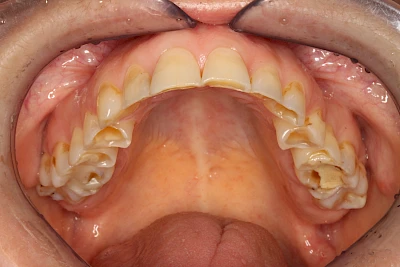

Über die Zeit können verschiedene Prozesse die Zahnhartsubstanzen aufzehren:

- Abnutzung durch Kauen (Abrasion) oder duch durch übermäßiges Knirschen bzw. Pressen (Attrition)

- Säurebedingte Auswaschung (Erosion)

Auswaschung (Erosion) dagegen ist eine Verschleißerscheinung der Zähne aufgrund von immer wiederkehrenden Säureangriffen durch die Nahrung, verstärkt zum Beispiel durch den Genuss säurehaltiger Getränke oder Speisen. Auch bei Menschen mit einer Essstörung (z. B. Bulimie) können die Zähne durch die Magensäure ausgewaschen erscheinen.

Eine Sonderform sind sogenannte keilförmige Defekte im Bereich der Zahnhälse. Hier geht man davon aus, dass Knirschen und Pressen in Kombination mit falschen Putzgewohnheiten (zu hoher Putzdruck, Verwendung von Zahnpasta mit hohen Abrasionswerten) eine Rolle spielen.